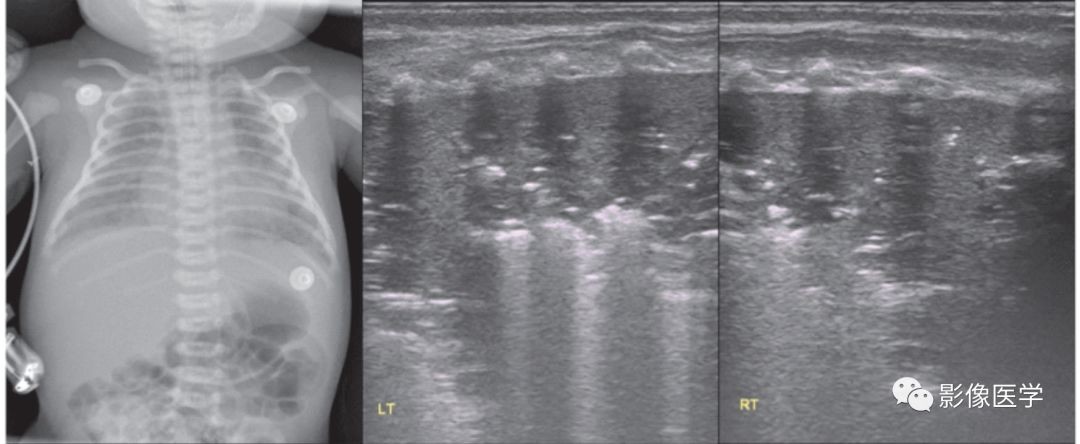

图6-25 感染性肺炎(4)

患儿系胎龄27+6周早产儿,自然分娩,出生体重1 070g。因早产、低出生体重入院。母亲患真菌性阴道炎,患儿出生后1周左右出现鹅口疮,并很快出现呼吸困难、发热等临床表现,肺部听诊可闻及湿啰音。肺脏超声(探头与肋骨平行扫描)显示双肺实变伴支气管充气征,边界欠规则。血培养3次、深部痰培养1次均培养出白色念珠菌,提示该患儿可能为白色念珠菌性肺炎。该病例同其他细菌感染性肺炎比较,在超声影像上并无差异。